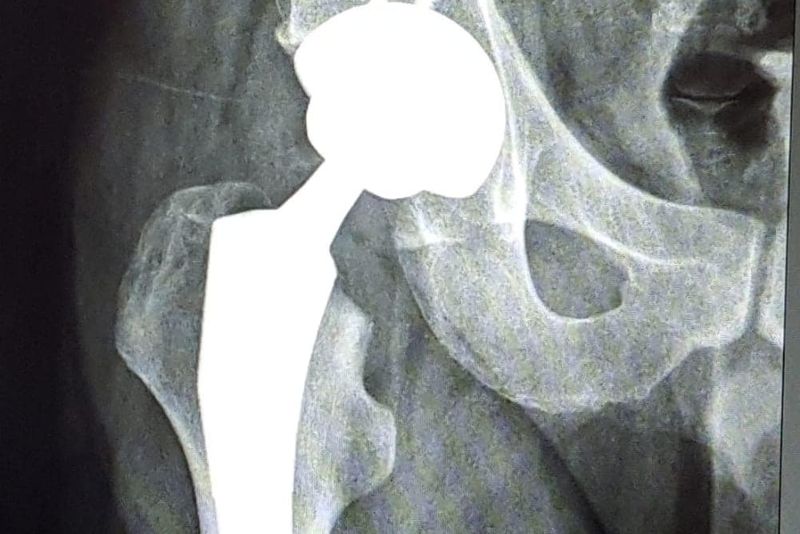

Premieră în medicina bistrițeană! Unui tânăr i-a fost redată mobilitatea șoldului

Potrivit managerului unității spitalicești bistrițene, o echipă mixtă, coordonată de dr. Remus Opriș - medic primar Ortopedie și Traumatologie, șef lucrări în cadrul UMF Târgu Mureș și dr. Bogdan Bumbu - medic primar Ortopedie și Traumatologie, șef secție, a realizat prima artroplastie totală de șold, utilizând o endoproteză totală necimentată, cuplu ceramică-ceramică.[gallery size="full" td_select_gallery_slide="slide" ids="80159,80161"]Pacientul a fost un tânăr diagnosticat cu coxartroză secundară NACF, stadiul V. STEINBERG.